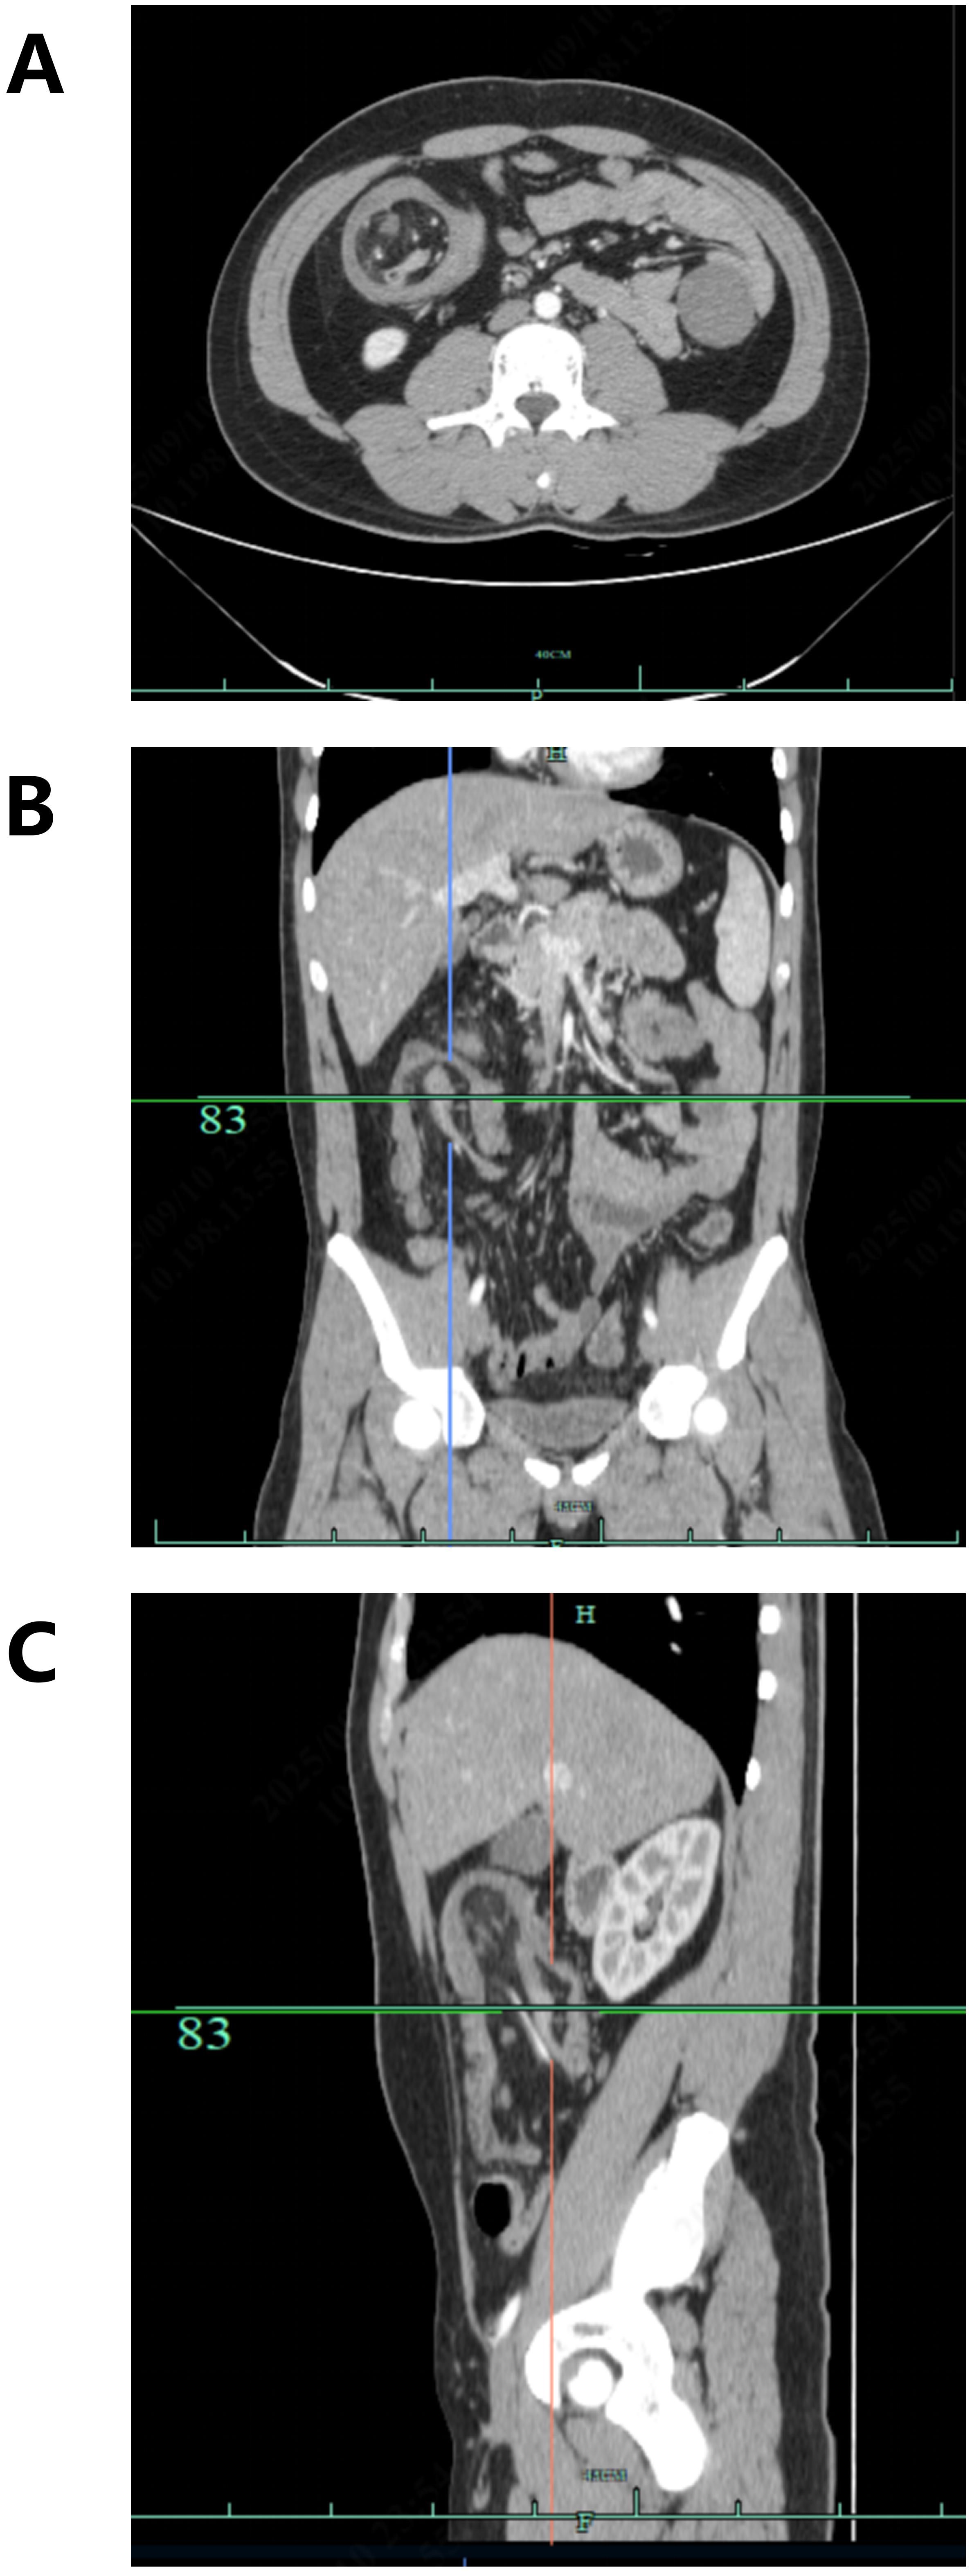

Background: Intussusception in adults is rare and often associated with underlying pathology such as tumors. Its coexistence with colorectal cancer(CRC) in young patients presents unique diagnostic challenges, as imaging may suggest separate lesions rather than a single malignancy. Case presentation: A 21-year-old male presented with worsening right upper and central abdominal pain. The contrast-enhanced abdominal CT suggested that the intussusception at the ileocecal region might be caused by a lipoma and revealed a separate mass in the transverse colon. Emergency laparoscopic exploration and subsequent open laparotomy confirmed a 4.0×5.0 cm cauliflower-like adenocarcinoma originating from the ileocecal region, which had caused the intussusception and mimicked separate pathologies on imaging. Conclusions: This case highlights the diagnostic complexity of synchronous intestinal lesions in young patients. It underscores the need for heightened suspicion of underlying malignancy when encountering intussusception and emphasizes the limitations of imaging in accurately characterizing complex bowel pathology.